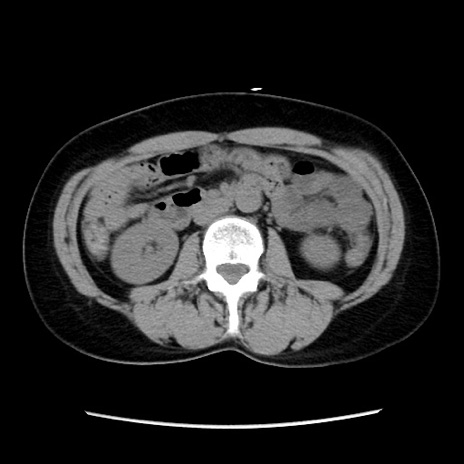

症例10(横断像)

【症例】 50歳代女性

【主訴】 腹痛

【現病歴】前日生レバーを食べた。今朝に排便あり。 昼前に突然発症の腹痛を生じ、当院救急外来を受診した。

【既往歴】 子宮筋腫にてで子宮全摘後

【身体所見】 意識清明、腹部:平坦、軟、下腹部やや左を中心に圧痛・反跳痛あり、筋性防御あり

【データ】WBC 7800、CRP 0.07